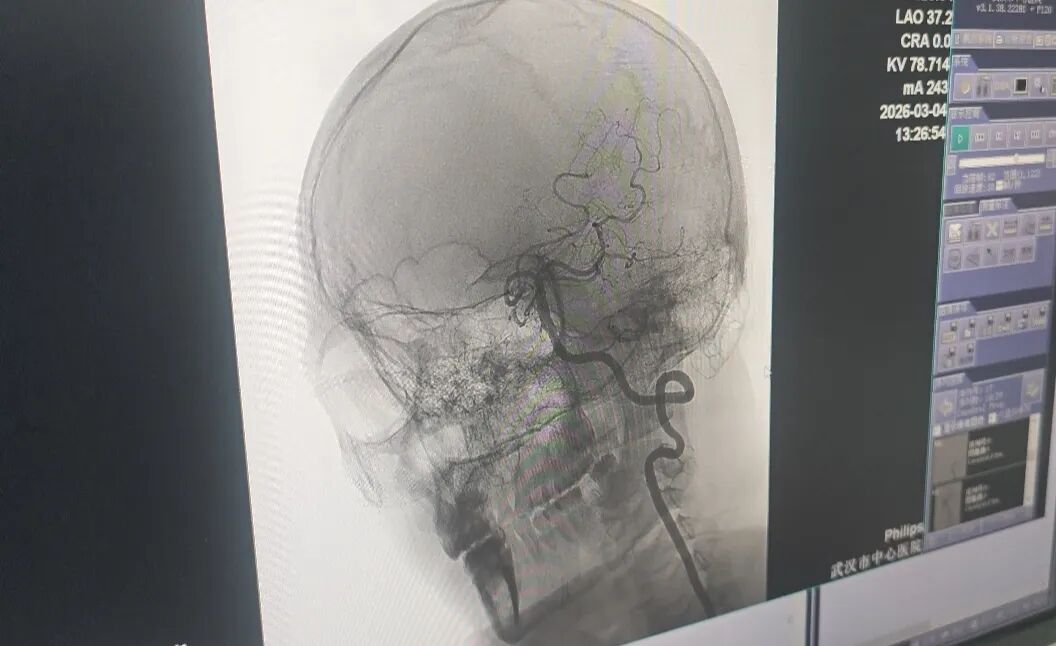

医生精准打通王先生堵塞的血管。记者李慧紫 摄

医院立刻开通卒中绿色通道,完善血管检查后发现,王先生并非常见的动脉硬化引发脑梗,而是椎动脉夹层造成了严重的血液动力学障碍,大血管被堵塞。如果不及时抢救,可能危及生命。

抢救团队考虑到患者椎动脉血管未完全闭塞,于是采用介入下动脉溶栓的方式,精准打通了堵塞的血管。